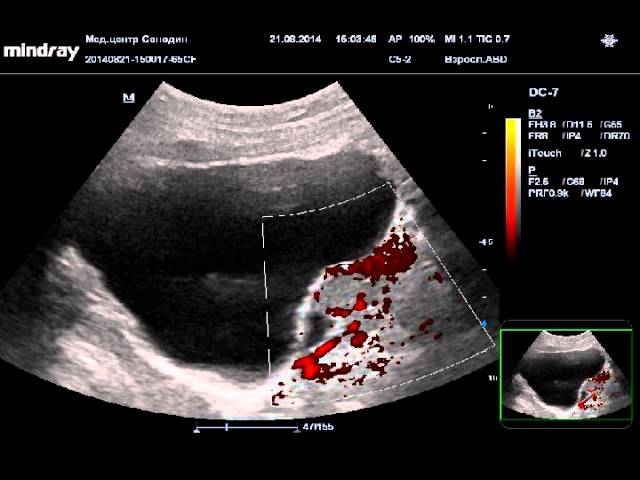

Смотрите в видео гипоэхогенное включение щитовидного хряща:

В видео новообразования в почке: